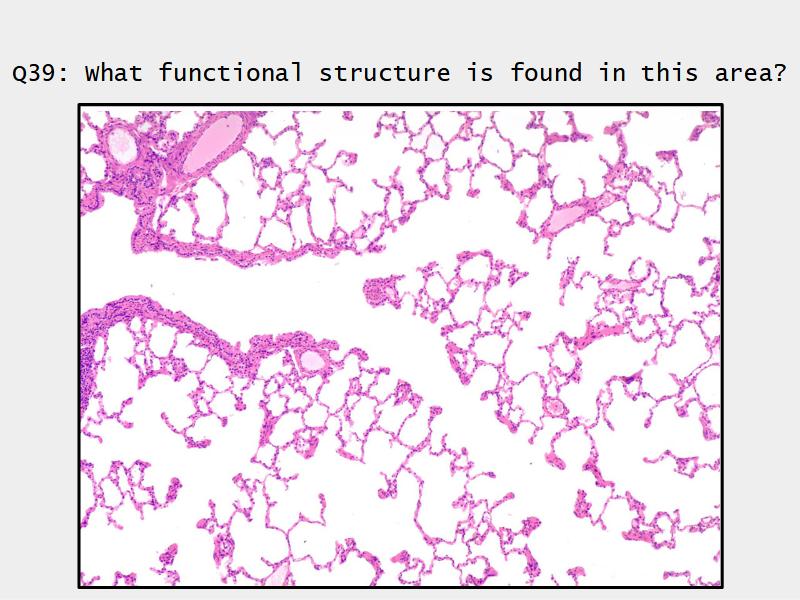

Components of the Blood-Air Barrier?

- Respiratory bronchioles

- Conducting -> Respiratory

- Simple cuboidal epithelium

- Secretory cells

- Alveoli

Lungs